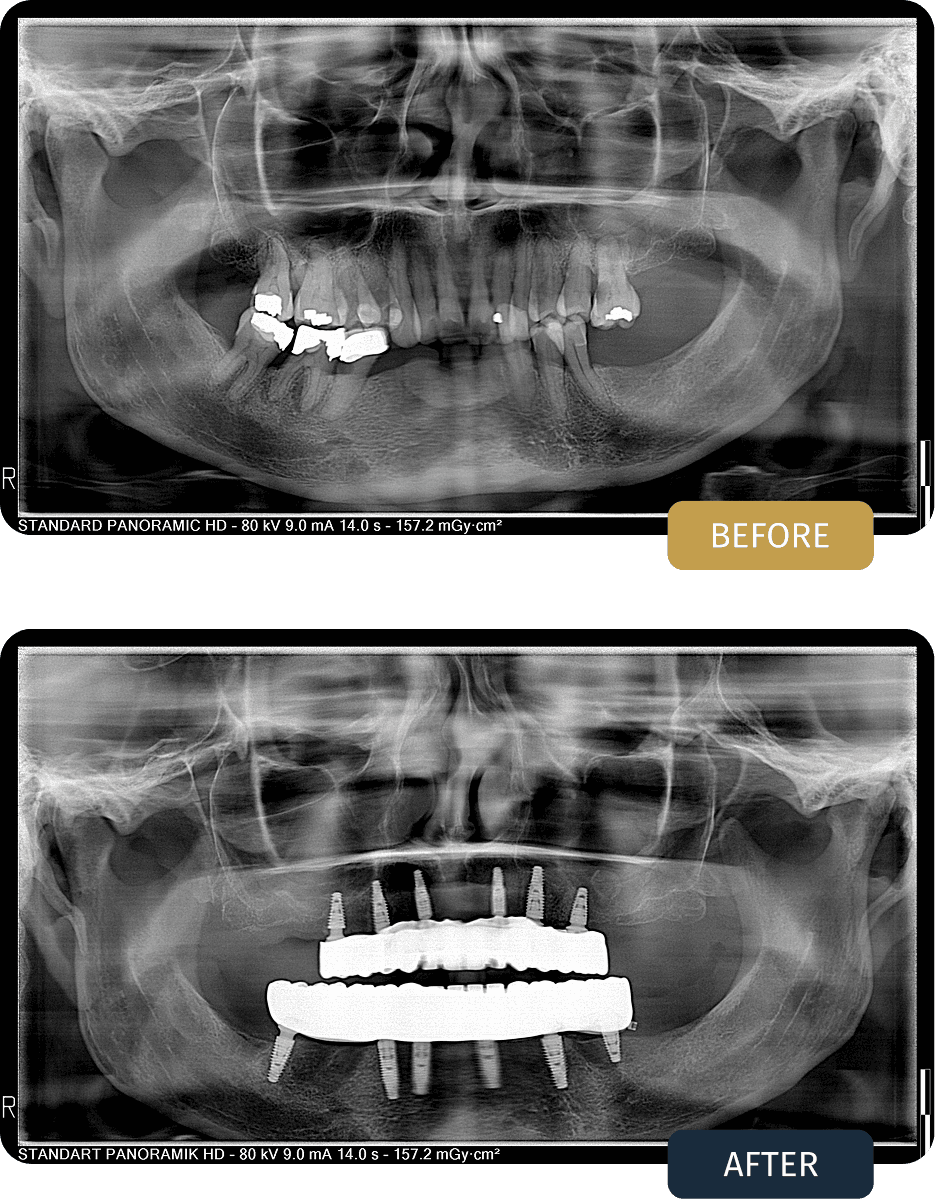

Susan presented with advanced tooth wear, failing restorations, and reduced bite stability in both jaws.

Clinical examination and panoramic imaging confirmed that the remaining teeth could not be predictably restored and that a full arch implant solution was required for both the upper and lower jaws.

Post treatment panoramic imaging confirmed stable implant positioning and accurate seating of the titanium bar supported prostheses in both jaws.

• Upper Jaw: All on 6 with Titanium Bar

• Lower Jaw: All on 6 with Titanium Bar

Both jaws were treated with an All on 6 implant protocol, using six strategically positioned implants per jaw to maximise bone support and load distribution.

Titanium bar supported fixed prostheses were selected for both arches to provide enhanced durability, precision fit, and long term biomechanical stability.